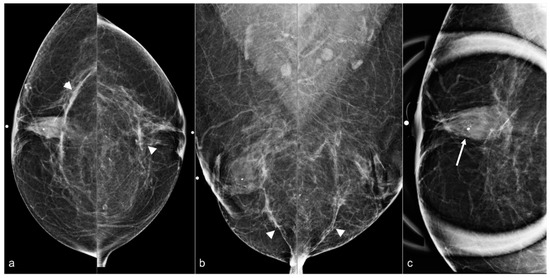

Figure 15. A 79-year-old woman with a history of subglandular silicone implants with a remote history of BES. Mammography (a) demonstrates dense masses in the left breast (arrows) and a right prepectoral asymmetry (arrowhead). Four biopsy clips are also seen in the left breast secondary to prior benign biopsies. Longitudinal left breast ultrasound (b) demonstrates an extensive snowstorm appearance, which limits evaluation of the breasts. T1-weighted post-contrast axial MRI (c) reveals an enhancing 0.3 cm focus in the right central breast (arrow). Subsequent MRI-guided biopsy revealed multifocal LCIS and ALH, and the patient underwent breast conservation therapy. Note the post-BES changes in the bilateral prepectoral regions (arrowheads), which is more pronounced in the left breast (d).